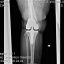

ALCUNE RADIOGRAFIE

» Immagine 11/14